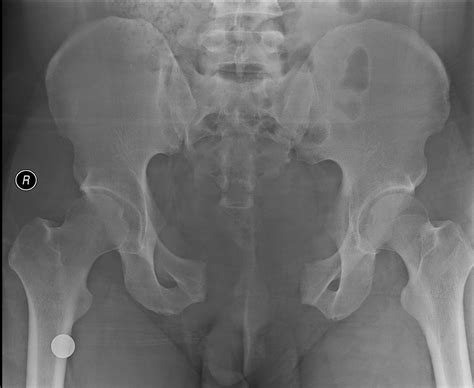

Open Book Fracture

An open book fracture, medically categorized as an anteroposterior compression pelvic ring injury, represents one of the most severe orthopedic emergencies a patient can face. The term derives from the anatomical appearance of the injury on an X-ray, where the pelvic ring disrupts at the pubic symphysis, causing the two halves of the pelvis to swing outward like the covers of an open book. Because the pelvis serves as the vital junction between the torso and the lower limbs and houses essential pelvic organs, this type of fracture requires immediate, highly specialized trauma care to prevent life-threatening complications such as massive internal hemorrhaging.

To confirm an open book fracture, clinicians rely on diagnostic imaging. An initial AP Pelvis X-ray is the gold standard for the first assessment. If the patient is hemodynamically stable, a CT scan is performed to provide detailed 3D imagery of the fracture patterns. This is essential for preoperative planning, as it allows surgeons to visualize the exact displacement of the bone fragments.